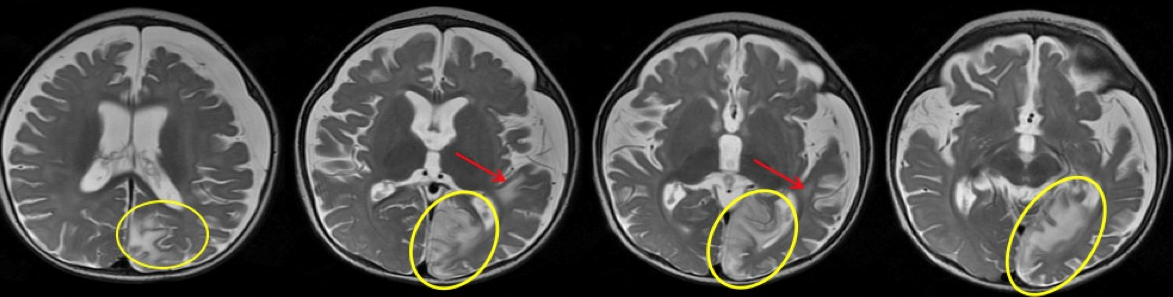

Clobazam was discontinued out of concern for possible drug-related adverse effects, but LFT results continued to remain elevated. The serum amylase level and abdominal ultrasonography findings were normal, which ruled out pancreatitis and other abnormalities of the hepatobiliary system. MRI with magnetic resonance spectroscopy of the brain (Figure 3) demonstrated a new area of involvement in the left occipital lobe.

Figure 3. New T2 hyperintensity involving the left occipital lobe and left angular/supramarginal region without associated restricted diffusion. Interval increased cerebral volume loss and development of bilateral subdural fluid collections are present, left greater than right.